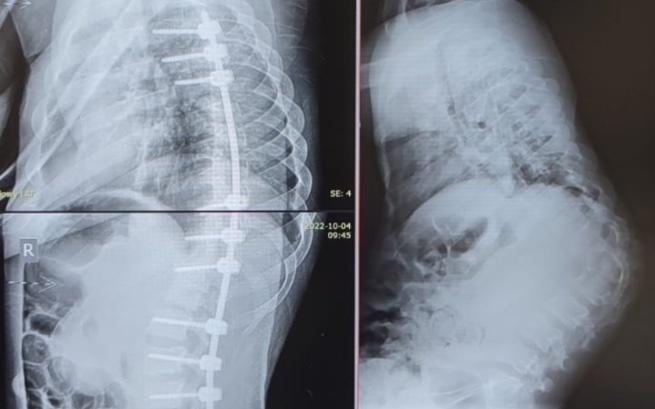

Mikołaj przeszedł operację kręgosłupa! To jednak nie koniec walki...

Mikołaj jest już po operacji kręgosłupa! W przyszłości czeka go prawdopodobnie kolejna, aby wzmocnić efekt pierwszej i zagwarantować stabilność kręgosłupa, ale już teraz cieszymy się z postępów!

Niestety, jednym z jego najpoważniejszych problemów jest ogromna skolioza kręgosłupa, która postępuje w zastraszającym tempie i z dnia na dzień ogranicza świat naszego małego wojownika. Żeby temu zapobiec i umożliwić Mikiemu jak najdłuższą sprawność fizyczną, potrzeba intensywnej rehabilitacji, która najpewniej będzie mu towarzyszyć do końca życia...